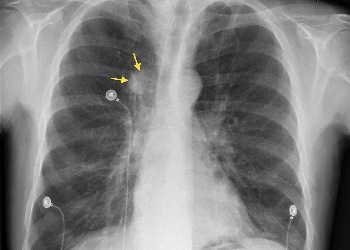

甲磺酸奥希替尼片(Osimertinib、奥希替尼、泰瑞沙、AZD9291),作为全球首个第三代EGFR-TKI抑制剂,自2017年3月在国内上市以来,已成为治疗局部晚期或转移性非小细胞肺癌(NSCLC)的重要方案。特别是对于存在表皮生长因子受体(EGFR)外显子19缺失或外显子21(L858R)置换突变的NSCLC患者,奥希替尼被视为一线治疗方案。奥希替尼因为远超同类的疗效,成为EGFR突变非小细胞肺癌当之无愧的首选“神药”!刚上市时,奥希替尼价格高达5万多,经过几轮的医保降价后,奥希替尼便宜很多,奥希替尼医保价格:奥希替尼的药房零售价格,各地存在差异。在国内,国产奥希替尼还未上市,进口奥希替尼医保报销后价格大约为5300元(80mg*30片),长期使用下来,负担比较重,很多患者把目光转向印度奥希替尼,因为印度奥希替尼价格便宜,并且印度奥希替尼效果和英国原厂进口保持一致,如今印度奥希替尼多少钱一瓶,印度奥希替尼多少钱一盒?印度奥希替尼一盒价格大约在每盒2880至3000元之间,一盒规格为80mg/粒,30片装。印度奥希替尼代购,印度奥希替尼哪里买?